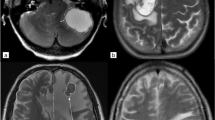

T1 weighted images as well as T2/FLAIR weighted images were co-registered to the corresponding ADC map sequence by using the software package statistical parametric mapping (SPM) [23]. Tumor segmentation was done by one person (LR) using a semi-automated active contour method (ITK-SNAP 2.0), which demonstrated excellent reliability and high efficiency of 3D segmentation [24]. The contrast-enhancing region in T1 weighted sequences, the non-enhancing T2 hyperintense region in T2/FLAIR weighted sequences, defined as peritumoral region (T2PZ) as well as the tumor- and edema-free gray and white matter compartment (GMWMC) were selected, representing three regions of interest. Contrast enhancing tumor regions and necrotic areas were excluded from the T2PZ. Within these three regions different ADC parameters were calculated using both MAtlab for first order and volumetric features and MaZda software package for textural features [25]. For a list of first order, volumetric and textural features please see Supplement 2. As studies have shown that the ADC may differ within the inner and outer border of the peritumoral region [17], we subdivided the peritumoral space into three adjacent ring-shaped spaces with an orthogonal diameter of each 3 mm, calculated the mean ADC of each ring Fig. 1.

Segmentation, registration of T1 contrast enhancing MR images as well as T2 images zo corresponding apparent diffusion coefficient (ADC) maps. We subdivided the peritumoral space into three adjacent ring-shaped spaces with an orthogonal diameter of each 3 mm and calculated the mean ADC of each ring as well as the ADC slope from the outer to the inner ring